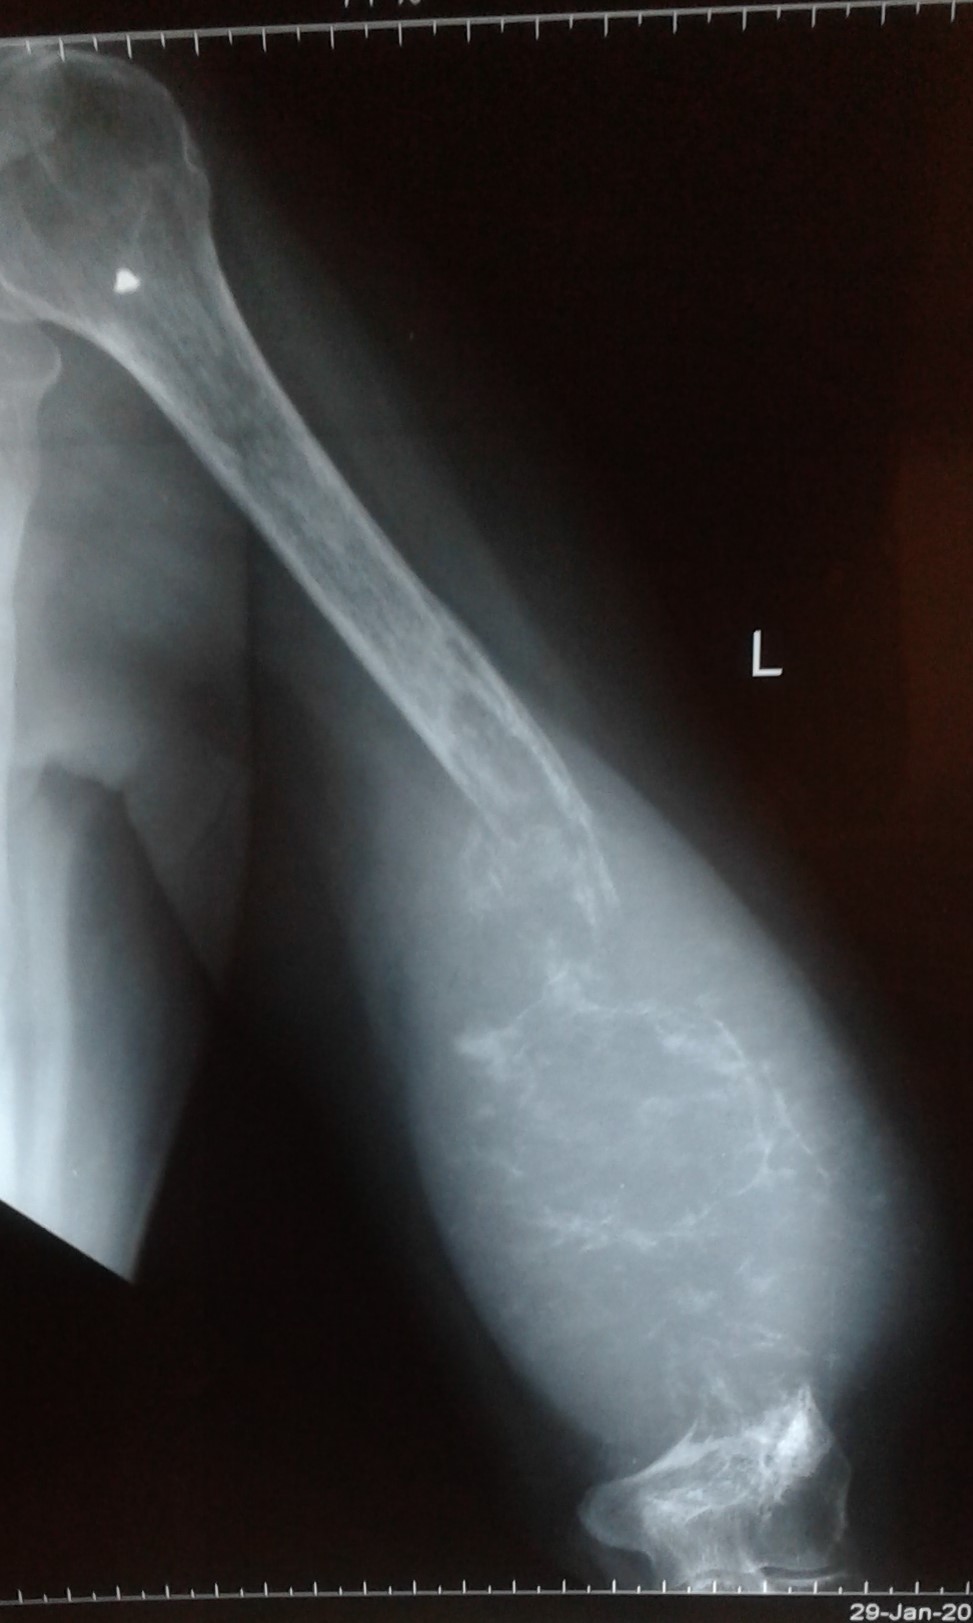

- Figure 2. Plain radiograph of left humerus showing juxta-articular_ expansile_ and lytic lesion of the distal humerus with soap